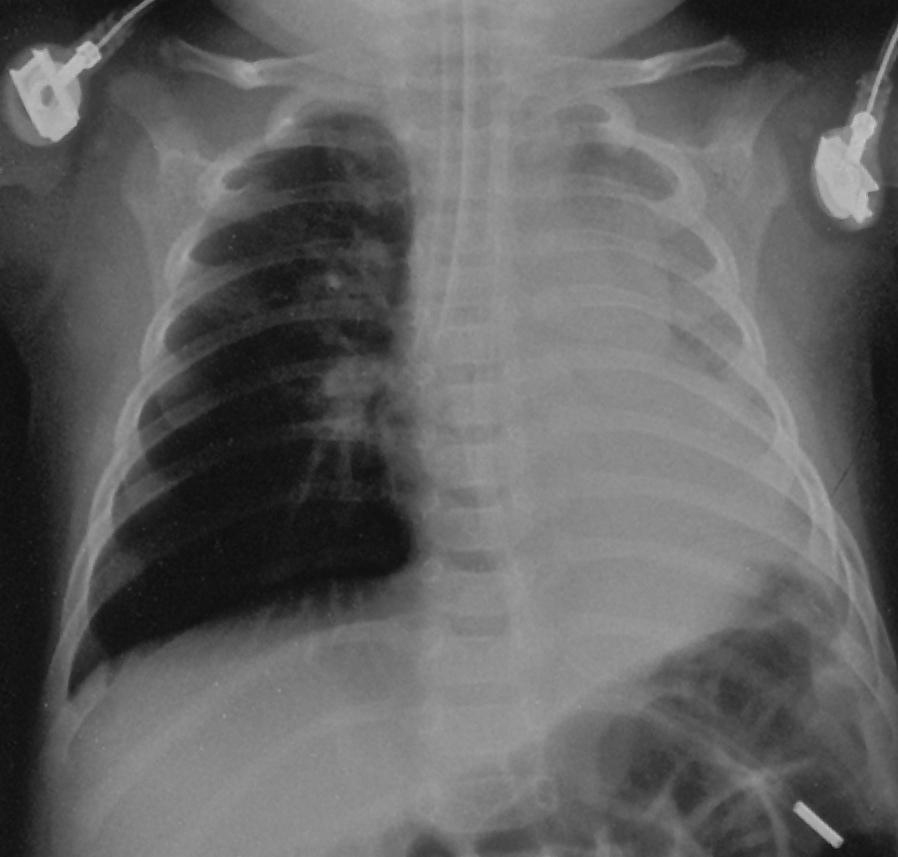

RMB Intubation, Left Collapse